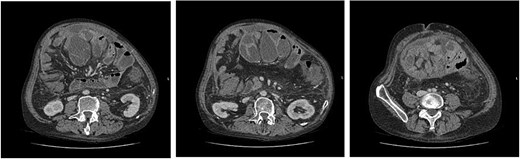

Abdominal computed tomography (CT) scan revealed multiple dilated small bowel loops with air-fluid levels, encapsulated within thickened peritoneum. There were collapsed bowel loops distally, consistent with an acute small bowel obstruction (Fig. 1). This was associated with trace-free fluid and no features of ischaemic bowel or pneumoperitoneum. A radiological diagnosis of SEP was made.

(left to right–cranial to caudal) Axial contrast-enhanced CT images demonstrating dilated small bowel loops in the central abdomen, encapsulated in thickened peritoneum and with trace free fluid. Appearances are consistent with small bowel obstruction.